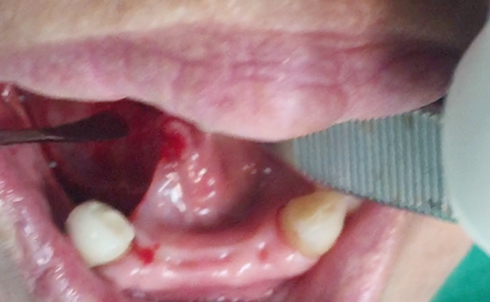

Partial edentulous clinical cases